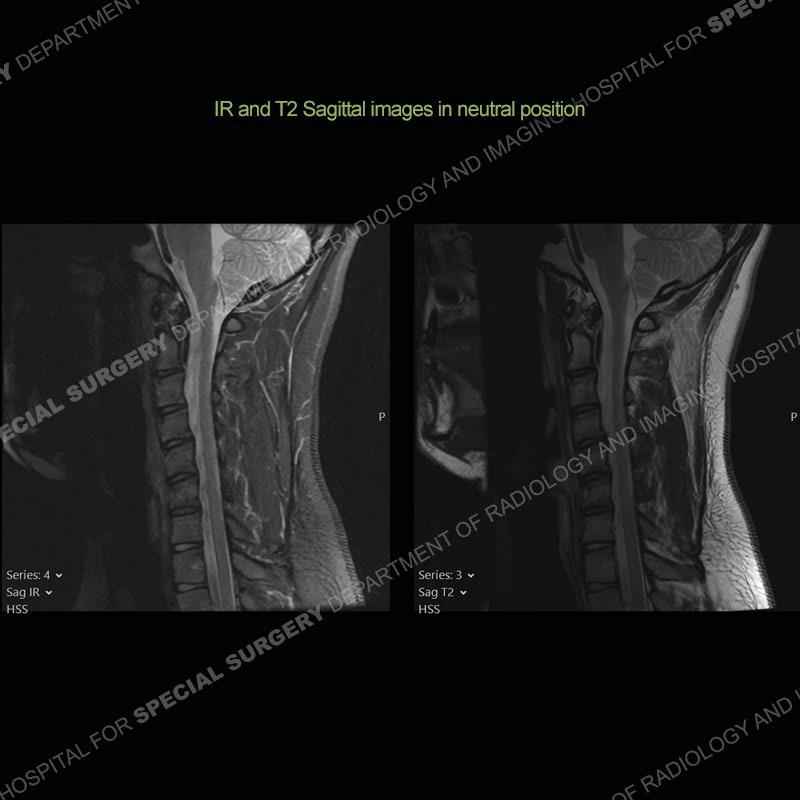

The images on the neutral sagittal images do not demonstrate any appreciable abnormality. On the flexion images, there is a forward displacement of the spinal cord centered on C6-C7. There is an expansion of the posterior dural sac which shows marked enhancement. Prominent flow voids are present of the expanded posterior dural sac on the T2 and T1 post contrast images.

Not present in this case, but frequently found is abnormal T2 signal intensity of the lower cervical cord about the area of maximum forward displacement. This can be seen on the neutral and flexed position imaging. Shown well in this case is the marked, crescentic expansion of the posterior dural sac. The sac shows marked enhancement with prominent flow voids and is often hyperintense on T1 and T2 images. The spinal cord as shown in this case is typically anteriorly displaced about the lower cervical cord.